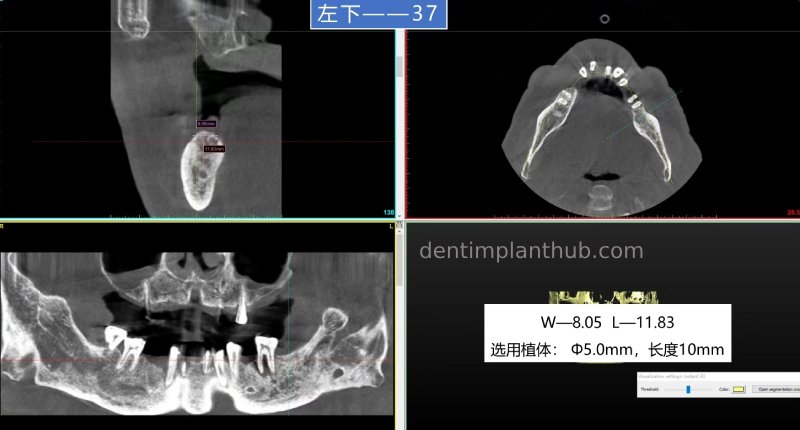

Status of individual loci to be planted and integration options

37, can be done without implantation;